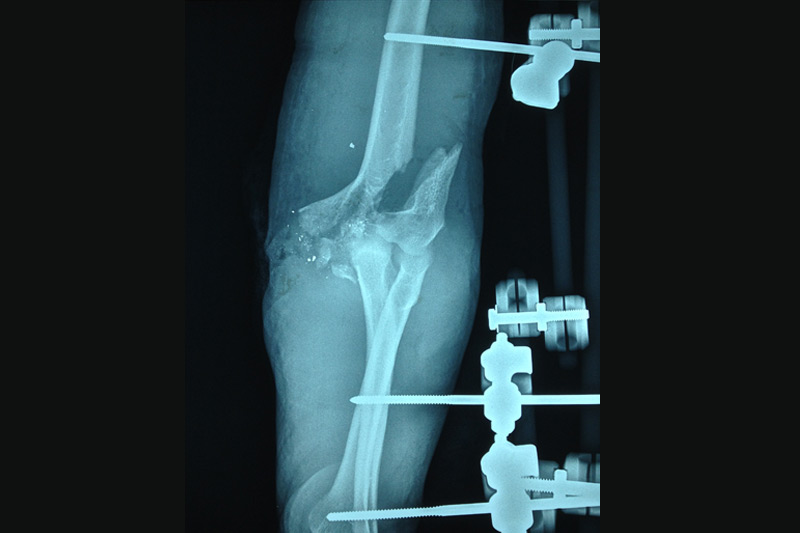

Debido a los accidentes de tránsito, a diario las personas sufren fracturas y lesiones de alto impacto, se otorga manejo de estas lesiones con implantes y material de osteosíntesis restableciendo la anatomía.